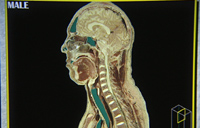

The "Visible Man"

Joseph Paul Jernigan war 39 Jahre alt, als man ihn 1993 in Huntsville, Texas, hinrichtete. Zehn Minuten nach der tödlichen Injektion wurde er von den Wissenschaftlern Dr. Spitzer und Dr. Ackerman in Empfang genommen, nach Denver transportiert, in blaue Gelatine eingefroren und während vier Monaten millimeterweise abgehobelt und fotografiert.

Bei seiner Verurteilung hatte niemand geahnt, dass Jernigan einmal als "Visible man" im Internet auferstehen würde: Als erster vollständig digitalisierter Mensch, als Projekt des dritten Jahrtausends, als Prototyp menschlicher Anatomie. Auch Jernigan wusste von nichts: Das weltweit verbreitete "Visible Human Project" ist das Resultat eines einzigartigen Zusammenspiels von Justiz und Wissenschaft, von Familienschicksal und amerikanischer Karriereplanung, von individueller Ohnmacht und gesellschaftlichem Ehrgeiz.

Joseph Paul Jernigan war 39 Jahre alt, als man ihn 1993 in Huntsville, Texas, hinrichtete. Zehn Minuten nach der tödlichen Injektion wurde er von den Wissenschaftlern Dr. Spitzer und Dr. Ackerman in Empfang genommen, nach Denver transportiert, in blaue Gelatine eingefroren und während vier Monaten millimeterweise abgehobelt und fotografiert.

Bei seiner Verurteilung hatte niemand geahnt, dass Jernigan einmal als "Visible man" im Internet auferstehen würde: Als erster vollständig digitalisierter Mensch, als Projekt des dritten Jahrtausends, als Prototyp menschlicher Anatomie. Auch Jernigan wusste von nichts: Das weltweit verbreitete "Visible Human Project" ist das Resultat eines einzigartigen Zusammenspiels von Justiz und Wissenschaft, von Familienschicksal und amerikanischer Karriereplanung, von individueller Ohnmacht und gesellschaftlichem Ehrgeiz.